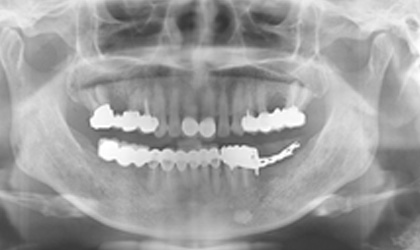

設計問題-力學考量 / 型態 / 咬合

長牙橋導致蛀牙-案例一

長牙橋導致蛀牙 - 案例二

長牙橋導致蛀牙 - 案例三

懸臂牙橋導致牙齒斷裂 ( 對側無牙 )